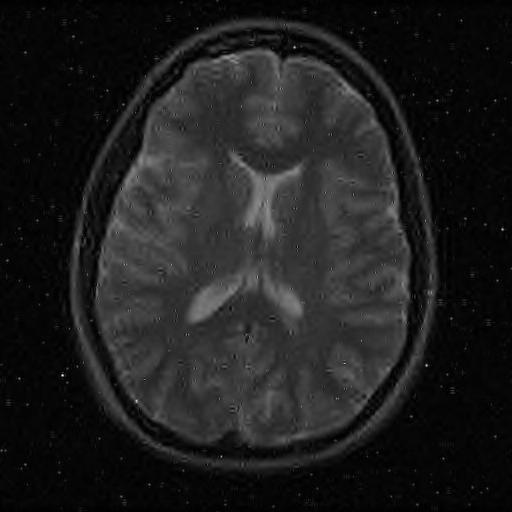

6.3. MR Image reconstruction

The second imaging application is concerned with medical imaging. Following the ideas from [32, 34], we simulate a multi-channel MRI sensing set-up, first using the same sine waves as in the previous experiment (results displayed in Fig 10), and then using spherical beam pattern (see in Fig. 11 for the results). We generate the classical Shep-Logan phantom, and set its dimension to .

The first experiment, depicted in Fig. 10 shows the results obtained by our method when using a Daubechies 4 sparsifying dictionary. Our results are compared to the single sensor analysis, and the results obtained by the Sum-of-Squares recovery [34, 32].

The recovery is obtained from noisy measurements, in which some additive Gaussian noise with variance has been added. The measurements are obtained by subsampling ( samples) of the Fourier transform. We see here that the fused compressed sensing is better capable of handling a multi-channel problem with unusual illumination (compared to the Sum-of-Squares method). Moreover, more details are preserved, when compared to the single sensor analysis method.

Some noise still appears in the image, but can easily be thresholded further if needed. One important aspect of MR Images that hasn’t been considered in this research, is the fact that they are sparse in gradient. One usually prefers to minimize the Total Variation instead of the norm or another frame using analysis.

Although we have not explicitly written the theory here, the recovered images in Fig. 11 show the results when using a TV minimization instead of the analysis.

The results were obtained from a spherical beam illuminating the input image. The measurements are obtained by sampling ( samples) of the Fourier coefficients at random iid from a Gaussian distribution. Again, some Gaussian noise with variance is added to every measurements.

As presented in these examples, our method is capable of handling highly complex signals in potentially many dimensions yet keeping a very low number of samples taken. We can also empirically verify that the presented approach enjoys more robustness to noise and variations in scene illuminations than other known methods.

This behavior is true for both images, which are real-world images of brain scans. It is worth keeping in mind that SSIM is a structural similarity which tries to emulate the human visual perception while the other metrics are pure machinery. As can be seen both from the figures and the tables, the proposed method performs at least as well as previous approaches, and may behave better when considering total variation minimization.